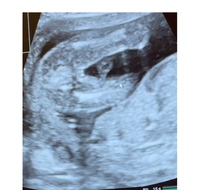

このエコー写真から性別分かりますか ちなみに妊娠16週です 女の子 Yahoo 知恵袋

このw、dとは、w=week、d=dayのことで、例えば妊娠16週1日なら「16w1d」となります。 これを知っておくと、後からエコー写真を見返した時にいつのものだったかがわかりますね。 FEW FEWは赤ちゃんの推定体重です。以下で説明する、赤ちゃんの頭、お腹、大腿骨の長さから計算されます。 この 性別が判明 妊娠16週目のエコー写真 D1=877cm 性別が判明 左写真では目や口元がわかり、顔がちゃんと確認できます。右写真は足がうつっています。足の間が開いた状態であったため、これを見て先生は「今のところ女の子だね」と性別を教えてくれました。夫婦ともに第1子は女の子 妊娠初期4週から7週|妊娠2ヶ月目|体調の変化やママの状態、お腹の赤ちゃ 妊娠・出産 胎児(お腹の赤ちゃん)の成長の経過|初期から臨月のエコー写真まとめ写真 妊娠・出産 葉酸は妊娠ママの必須栄養素!葉酸の効果。食品